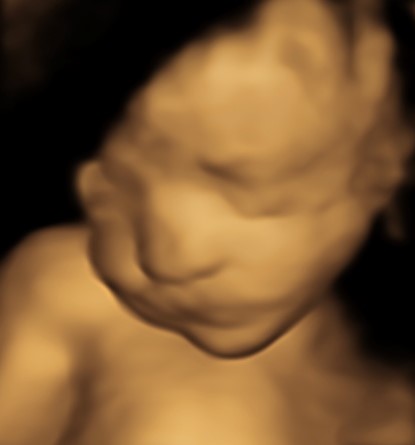

4D/5D/HD Ultrasound Gallery

Gallery